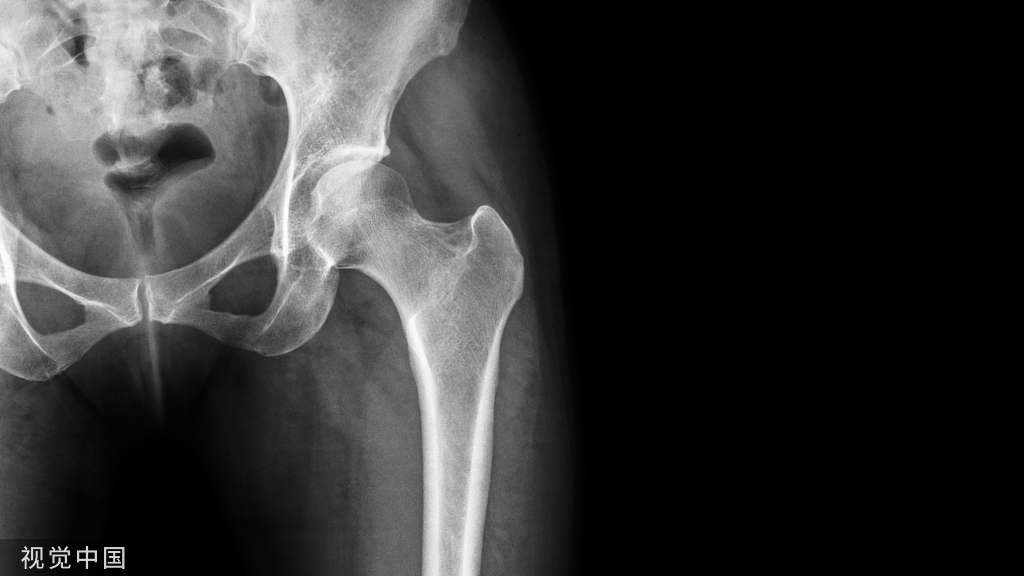

股骨转子间骨折行PFNA内固定,自螺旋刀片注入骨水泥增强。